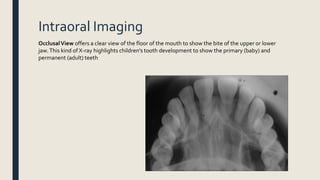

Intraoral Imaging

OcclusalView offers a clear view of the floor of the mouth to show the bite of the upper or lower

jaw.This kind of X-ray highlights children’s tooth development to show the primary (baby) and

permanent (adult) teeth